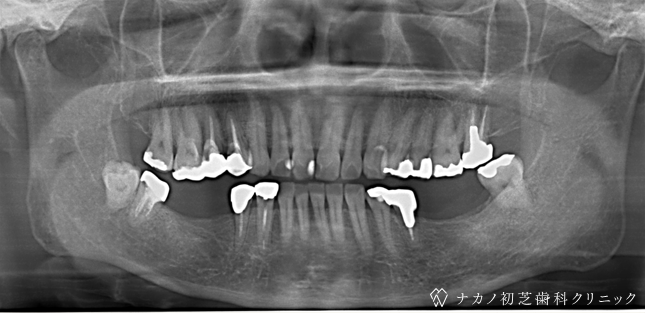

インプラント・13本 (60代女性)

BEFORE

AFTER

年齢 60代女性

治療内容 インプラント治療13本(骨造成の併用)

インプラント治療とは、歯を抜いた所にチタン製の人工歯根を埋入し、その上に歯を入れる方法です。骨を増やすことで、より審美的に治療が出来ました。費用 1本 400,000円(税込 440,000円)

リスク・副作用

腫れ・疼痛・違和感を感じるなどの症状を生じることがあります。